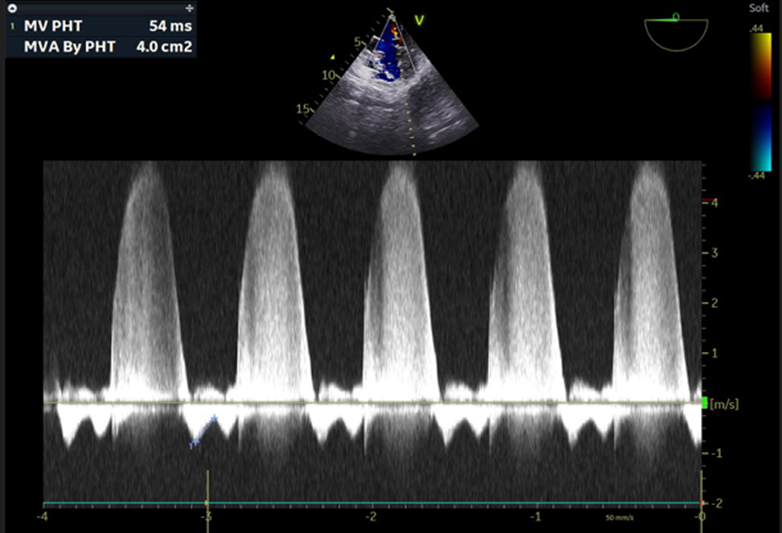

PCWP also revealed a large A wave suggestive of mitral regurgitation. A gastric tube was inserted to aspirate the stomach secretions and air and removed, and an adult TEE probe (GE, 6TC-RS, Vivid T9 v205, Norway) was inserted. Anesthesia was maintained with 60% oxygen in the air, sevoflurane 0.75- 1.5 % and vecuronium infusion (2mg/hr) with intermittent fentanyl and midazolam boluses. [9] She was positioned prone for the surgical procedure. External defibrillator pads were applied before turning the patient prone, and all resuscitation and antiarrhythmic drugs were kept ready to tackle an inadvertent arrhythmic event. The TEE was performed in the supine position and continued in the prone position with a little technical difficulty. TEE revealed an EF of 36%, fractional shortening (FS) of 17 Percent sign after inodilator support, severe MR with central jet, MR flow velocity > 5 m/sec and vena Contracta of 0.8mm(Figure 3a,b) and CO of 2.65 L/M2, mitral valve area of 4.3cm2 by planimetry, LA -31mm. (Figure 4) In addition LV basal wall aneurysmal, hypokinesia of basal, posterior and inferior LV wall, and no thrombus in LV(Figure 5a,b) and LV type 1, diastolic dysfunction (E Less-than sign)

HR-heart rate, BP-blood pressure, MAP- mean arterial pressure, SPO2- arterial oxygen saturation, PAP-pulmonary artery pressure, CVP- central venous pressure, PCWP- Pulmonary Capillary Wedge Pressure, MPAP- mean pulmonary artery pressure, SVR- systemic vascular resistance, CO- cardiac output, PVR- pulmonary vascular resistance, EF- ejection fraction, RA- room air, SvO2- mixed venous oxygen saturation PCWP also revealed a large A wave suggestive of mitral regurgitation. A gastric tube was inserted to aspirate the stomach secretions and air and removed, and an adult TEE probe (GE, 6TC-RS, Vivid T9 v205, Norway) was inserted. Anesthesia was maintained with 60% oxygen in the air, sevoflurane 0.75- 1.5 % and vecuronium infusion (2mg/hr) with intermittent fentanyl and midazolam boluses. [9] She was positioned prone for the surgical procedure. External defibrillator pads were applied before turning the patient prone, and all resuscitation and antiarrhythmic drugs were kept ready to tackle an inadvertent arrhythmic event. The TEE was performed in the supine position and continued in the prone position with a little technical difficulty. TEE revealed an EF of 36%, fractional shortening (FS) of 17 Percent sign after inodilator support, severe MR with central jet, MR flow velocity > 5 m/sec and vena Contracta of 0.8mm(Figure 3a,b) and CO of 2.65 L/M2, mitral valve area of 4.3cm2 by planimetry, LA -31mm. (Figure 4) In addition LV basal wall aneurysmal, hypokinesia of basal, posterior and inferior LV wall, and no thrombus in LV(Figure 5a,b) and LV type 1, diastolic dysfunction (E Less-than sign

Figure-3b: The ME4C view (0°) 2D, TEE image displays that the CWD of the mitral valve revealed a flow velocity of 5.4 m/sec. and the velocity is thick, well enveloped and triangular suggestive of severe MR.

ME4C- mid esophageal 4 chamber view, CWD- continuous wave doppler, MR- mitral regurgitation